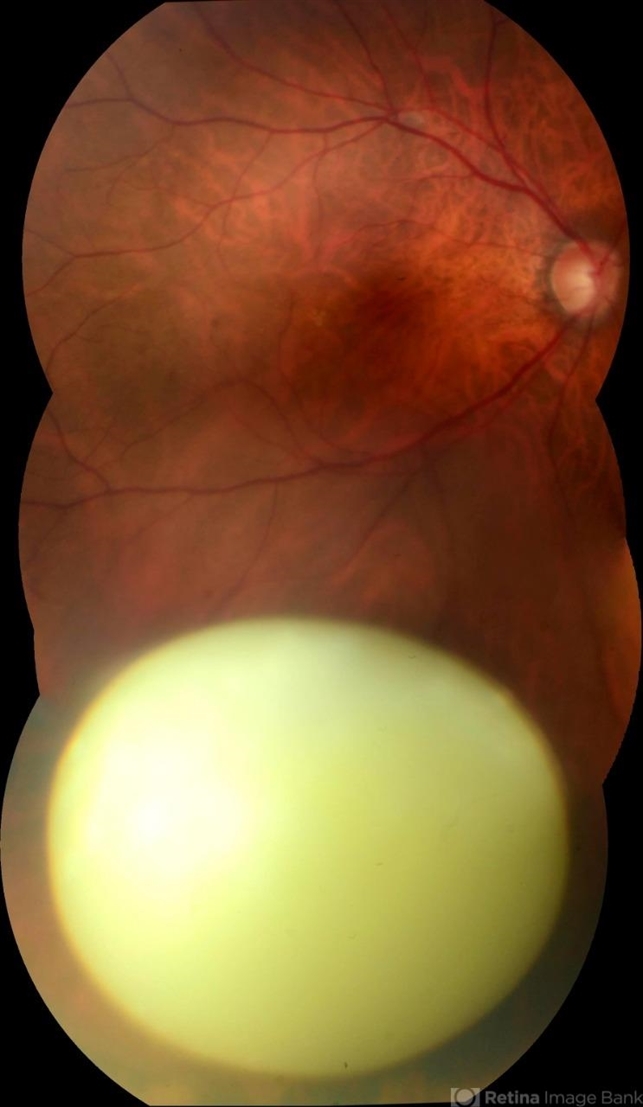

- dislocated crystalline lens

Topcon TRC-50 DX, Imaginet 5.0, angle de 50 graus. Flash 18W-S - Description

- Male patient 54-years-old. In the preoperative follow-up of cataract surgery, he suffered blunt trauma to the right eye, with a total dislocation of the lens.